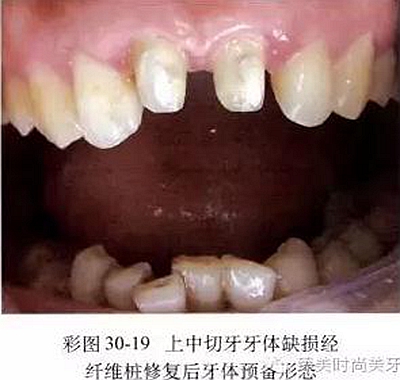

5.當(dāng)前牙牙體缺損大于1/3,并波及到牙髓時(shí),應(yīng)進(jìn)行完善的根管治療,然后采用成品纖維樁(如碳纖維樁、玻璃纖維樁、石英纖維樁)或二氧化鋯陶瓷樁放置在根管內(nèi)加強(qiáng)牙體組織的抗力,用與殘余牙體組織顏色相同的復(fù)合樹脂成核后按常規(guī)進(jìn)行牙體預(yù)備(彩圖30-19)。對(duì)于牙體缺損達(dá)到牙槽嵴頂時(shí),一般采用成品金屬樁樹脂核或鑄造陶瓷樁核進(jìn)行部分修復(fù),然后按常規(guī)進(jìn)行牙體預(yù)備。